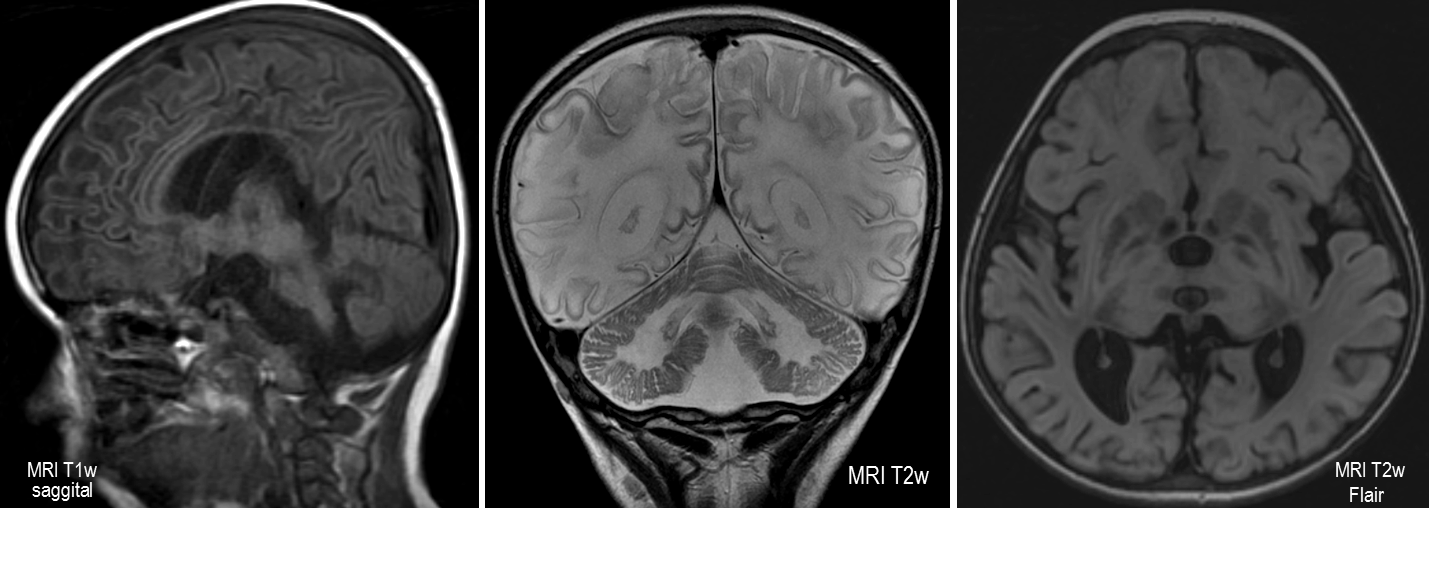

Болезнь тей 118 фото